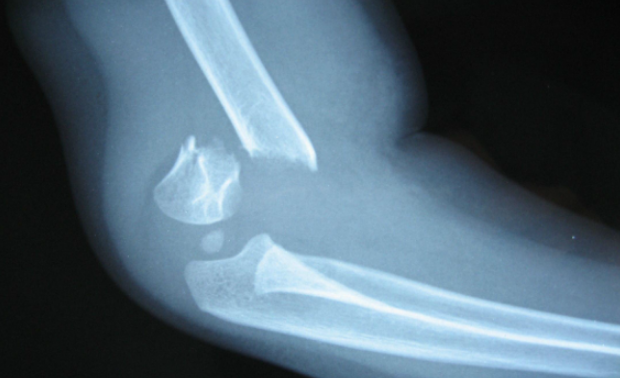

在我们的日常生活中,大多数人都知道骨折是怎么一回事了,骨折的发生,常常是因为剧烈的运动冲击、打架、车祸等等。骨折是指骨结构发生了破坏性的断裂,影响了骨结构的正常粘合状态,患者需要注意的是,发生骨折后必须马上采取治疗措施,不能根据自己或者其他普通人的判断来正骨和复位,应该立刻送医院治疗,根据正规医院的医生治疗的效果才能有保证哦。那么,一般骨折治疗的步骤和顺序都有哪些呢?这是很多患者都想知道的问题,因为它关乎着我们的行动,枣阳厚德康复医院骨科专家专家表示,骨折在平时的生活中是比较常见的,而它所带来的伤害也是很大的,因此治疗很重要。骨折后该如何治疗呢?

此方法主要是针对不开刀的骨折病人。骨折复位手法大致分为拔伸牵引、折顶回旋、旋转屈伸、提拉牵抖、端提挤捺等复位手法。在制定实施哪一种手法之前,一定要看片子,因为通过骨折后的片子,可以看出骨折的复位手法,所以骨折后的片子尤为重要,然后是选择治疗的复位手法,最为重要的是骨折复位手法技巧。

骨折手法复位的技巧主要是通过对骨折的精准判断和准确的对位。骨折部位与远端或近端的距离也决定手法复位。看片子时需要对骨折情况的深入了解,对位时需要根据相互的方向来精确的对位,并给骨折病人尽量减轻痛苦。要达到得心应手,手法的运用必须熟练、灵活、准确,做到伤员无痛苦感为好,手法的轻度适宜,对骨折的愈合迟速以及能否遗留残疾有着密切的关系。